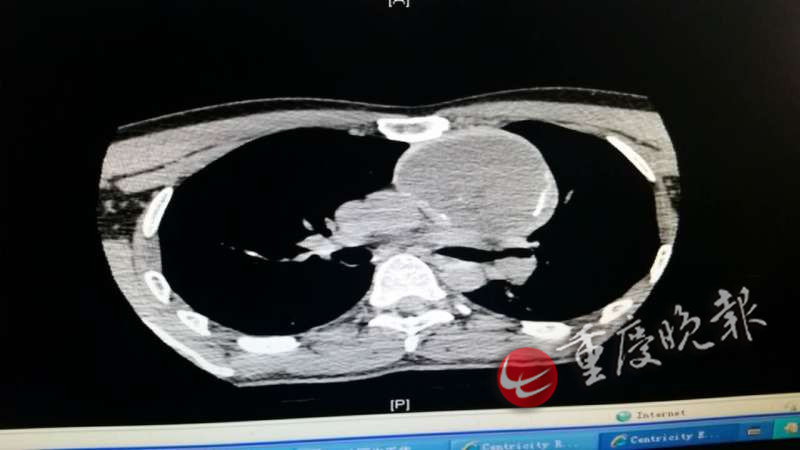

家住荣昌的徐先生告介绍,春节前,正在外地打工觉得自己肩部有点痛,以为是劳损引起的,就去做了按摩,贴了膏药,疼痛有所缓解,但几天后又疼痛不已,到医院检查胸片显示左侧胸腔有一个大包块。由于当地医院医疗条件有限,徐先生和家人一起到新桥医院作进一步检查,经过CT等检查显示,其左侧胸腔有8×7cm大小畸胎瘤。当医生告诉徐先生,这个畸胎瘤可能自他生下来就有,只是现在长大了而已。这让徐先生和家人吃惊不已,也深深感到害怕。

“畸胎瘤将左侧锁骨下下静脉、无名静脉“吞噬”了 8公分长,并且导致血流变慢,形成了血栓,血栓随时都可能脱落而致肺部栓塞、心衰等而危及生命。”新桥医院胸外科余祖滨副教授介绍,如果不手术,畸胎瘤将逐渐增大,进而“吞噬”主动脉、心脏等,那时就没法手术,所以尽快手术切除畸胎瘤是唯一的治疗方式。